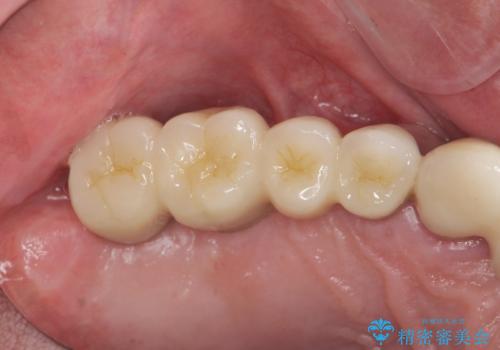

重度に吸収してしまった歯槽骨をしっかりと造成を行ったのちにインプラント治療を行ったので、安定した歯周環境にすることができました。